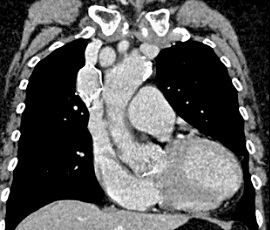

CT画像(1年後)